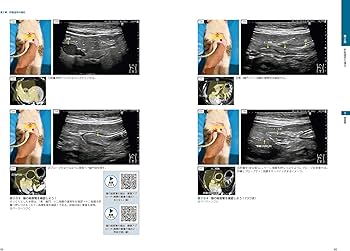

犬と猫の腹部超音波の描出レッスン 上・下巻 ビジュアルと動画でわかる! 犬と猫の腹部超音波の描出レッスン 下巻

裁断済のため状態を悪いとしています。犬と猫の腹部超音波の描出レッスン 上巻下巻2冊- タイトル: 犬と猫の腹部超音波の描出レッスン - 著者: 戸島雅史- 出版社: 緑書房